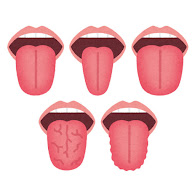

体調が丸わかり"危険な舌"の状態はこれだ 舌は「健康のバロメーター」週刊女性PRIME東洋経済オンライン。

白い、ガタガタ、ひび割れ 。“舌”でわかる体調不良のサインとは?田中友也さん 季節の養生法からだにいいこと。

見た目で健康かどうか、わかるの?2ページ目 :おとなのカラダゼミナール:日経Gooday グッデイ。

見た目で健康かどうか、わかるの?2ページ目 :おとなのカラダゼミナール:日経Gooday グッデイ。

舌のサイン 院長ブログ八尾市のオカモト鍼灸整骨院。

舌診~毎日鏡の前で健康チェックをしたくなる舌の状態を解説 祥泉針灸整骨院。

石豆。舌は健康のバロメーター三越前駅小伝馬町歯科 ハルデンタルオフィス。

舌で美容体質を知る方法2024 年のリアルなLemon8ユーザー体験。

石豆。舌は健康のバロメーター三越前駅小伝馬町歯科 ハルデンタルオフィス。